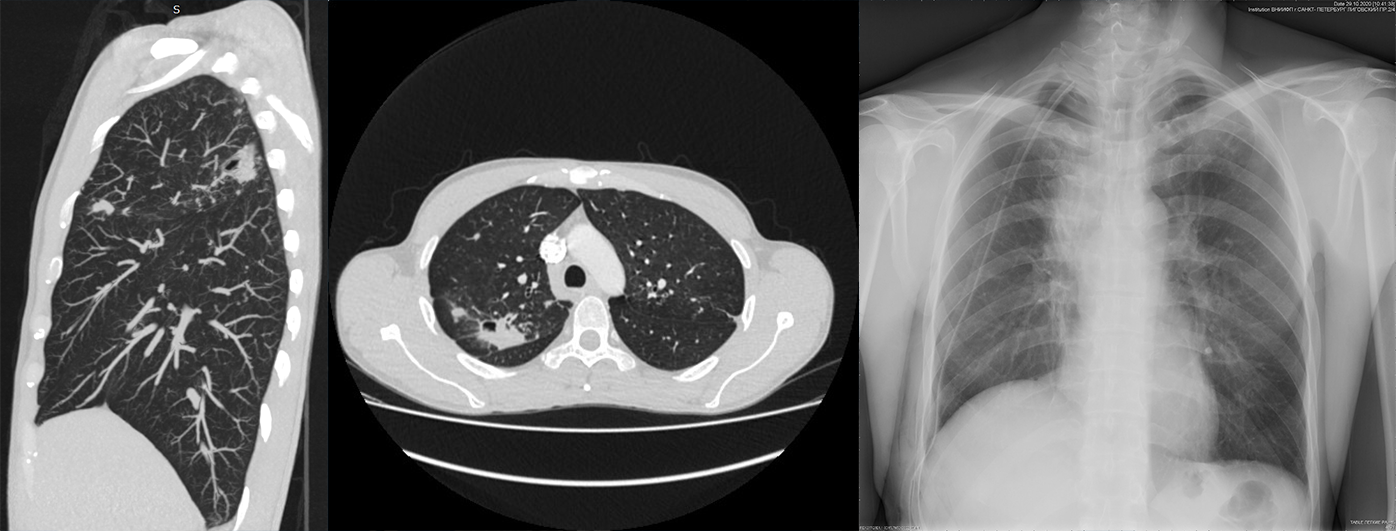

Больному с кавернозным туберкулезом верхней доли правого легкого, МБТ(-), ЛЧ МБТ выполнена робот-ассистированная верхняя лобэктомия справа. Консольное время операции составило 55 минут.

КТ-картина кавернозного туберкулеза верхней доли правого легкого с очагами отсева в пределах С1-С3.

На утро состояние пациента стабильное, переведен из ОРИТ в общую палату отделения госпитализации. По данным рентгенографии органов грудной клетки 29.10.2020 легкие расправлены, инфильтрации в легких, воздуха и жидкости в плевральной полости не выявлено.